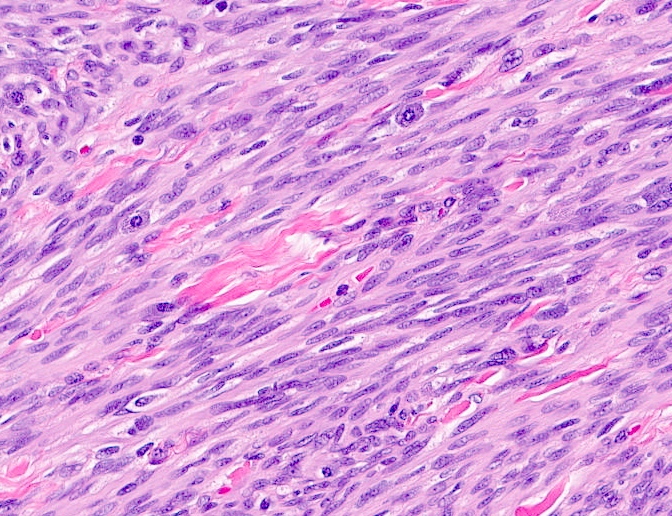

Microscopic (histologic) description

- Well circumscribed, lacks true capsule, rarely infiltrative

- Bland, uniform, short to elongated spindle cells arranged as short haphazard intersecting fascicles admixed with bands of hyalinized, brightly eosinophilic collagen and variable amounts of fat

- No more than mild nuclear atypia

- Mitoses usually absent, atypical mitoses and necrosis absent

- Mast cells common, perivascular lymphocytic infiltrates on occasion

- Focal myxoid stromal changes common

- May show smooth muscle leiomyomatous differentiation (elongated spindle cells with cigar shaped nuclei and pink cytoplasm)

- Rarely cartilaginous or osseous components

- Variants:

- Collagenized / fibrous: collagenous stroma predominates, may have hypocellular myofibroblastic spindle cell component

- Cellular: dense proliferation of myofibroblasts, ratio of spindle cells to collagen increased compared with classical variant, may have infiltrative borders, storiform or herringbone arrangement

- Infiltrative: irregular margins, grows into surrounding mammary parenchyma entrapping glandular tissue

- Myxoid: stellate and spindle cells in abundant myxoid stroma (Histol Histopathol 2016;31:1)

- Deciduoid: large round, polygonal cells with abundant eosinophilic glassy cytoplasm, single or multiple prominent nucleoli which may be eccentrically placed, binucleation, sharp cell borders, eosinophilic intracytoplasmic inclusions (Histopathology 2008;52:652)

- Lipomatous: abundant adipocytic component

- Epithelioid: oval to polygonal cells arranged in clusters, cords, alveolar groups, linear strands, mono, bi or multinucleated, may have eccentrically placed nuclei with small nucleoli, well defined cell borders, single file arrangement may mimic invasive lobular carcinoma (Am J Surg Pathol 2009;33:1085)

- Atypical: single or scattered atypical mono or multinucleated cells with mild to severe nuclear pleomorphism, regarded as degenerative (Arch Pathol Lab Med 2008;132:1813)

Microscopic (histologic) images